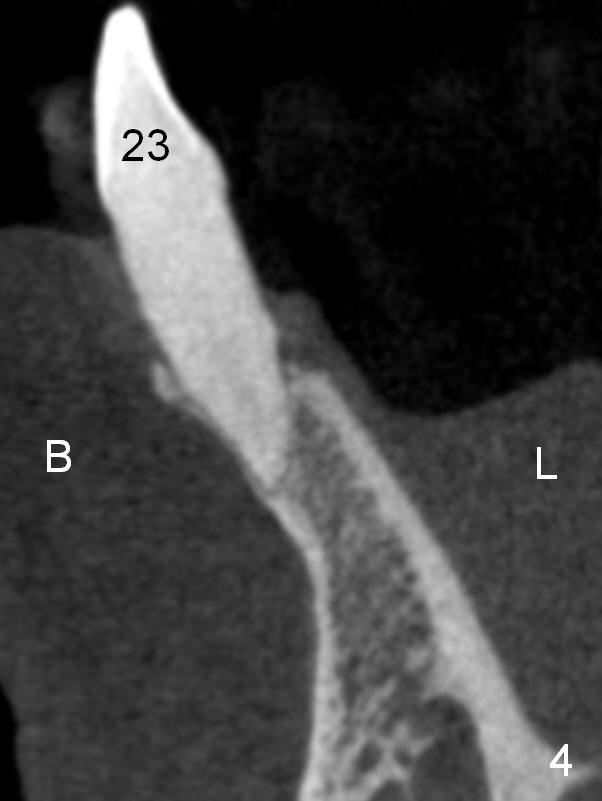

A 74-year-old man has several missing teeth (Fig.1). His 1st goal is to replace the lower left lateral incisor (Fig.2). The residual root has an apical lesion (Fig.3 *). To describe intraop findings, a CT image of a different patient is used (Fig.4 coronal section; B: buccal; L: lingual). After extraction, the buccal plate is found to be thin and low (Fig.5 arrowheads). A 1.5 mm pilot drill (Fig.6 red line) is used to initiate osteotomy in the lingual plate of the socket. Once the drill penetrates the lingual plate, the trajectory changes and the depth is 17 mm from the gingival margin (Fig.7). A PA is taken (Fig.8); it appears that the osteotomy can be extended more apically. When the pilot drill extends to 20 mm, there is sudden empty feeling. The lingual plate has perforated (Fig.9). A new osteotomy is established buccally (Fig.10 pink). To avoid buccal plate perforation, especially in the buccal undercut area (>), the coronal end of the drill has to be tilted buccally (<--). An angled abutment (3x20 mm, 15°) is placed (Fig.11,12). The abutment is modified (Fig.13,14) to accommodate an immediate provisional (Fig.15,16 P). Perio dressing is to be applied to prevent the bone graft from getting dislodged buccally (Fig.15). The dressing is in place 7 days postop (Fig.17).